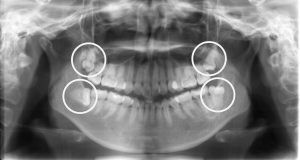

親知らずは抜かないと矯正治療はできないのですか?

矯正治療を考えているのですが親知らずが4本あるとかかりつけの歯医者さんで言われました。骨の中にあって口の中からは見えない…